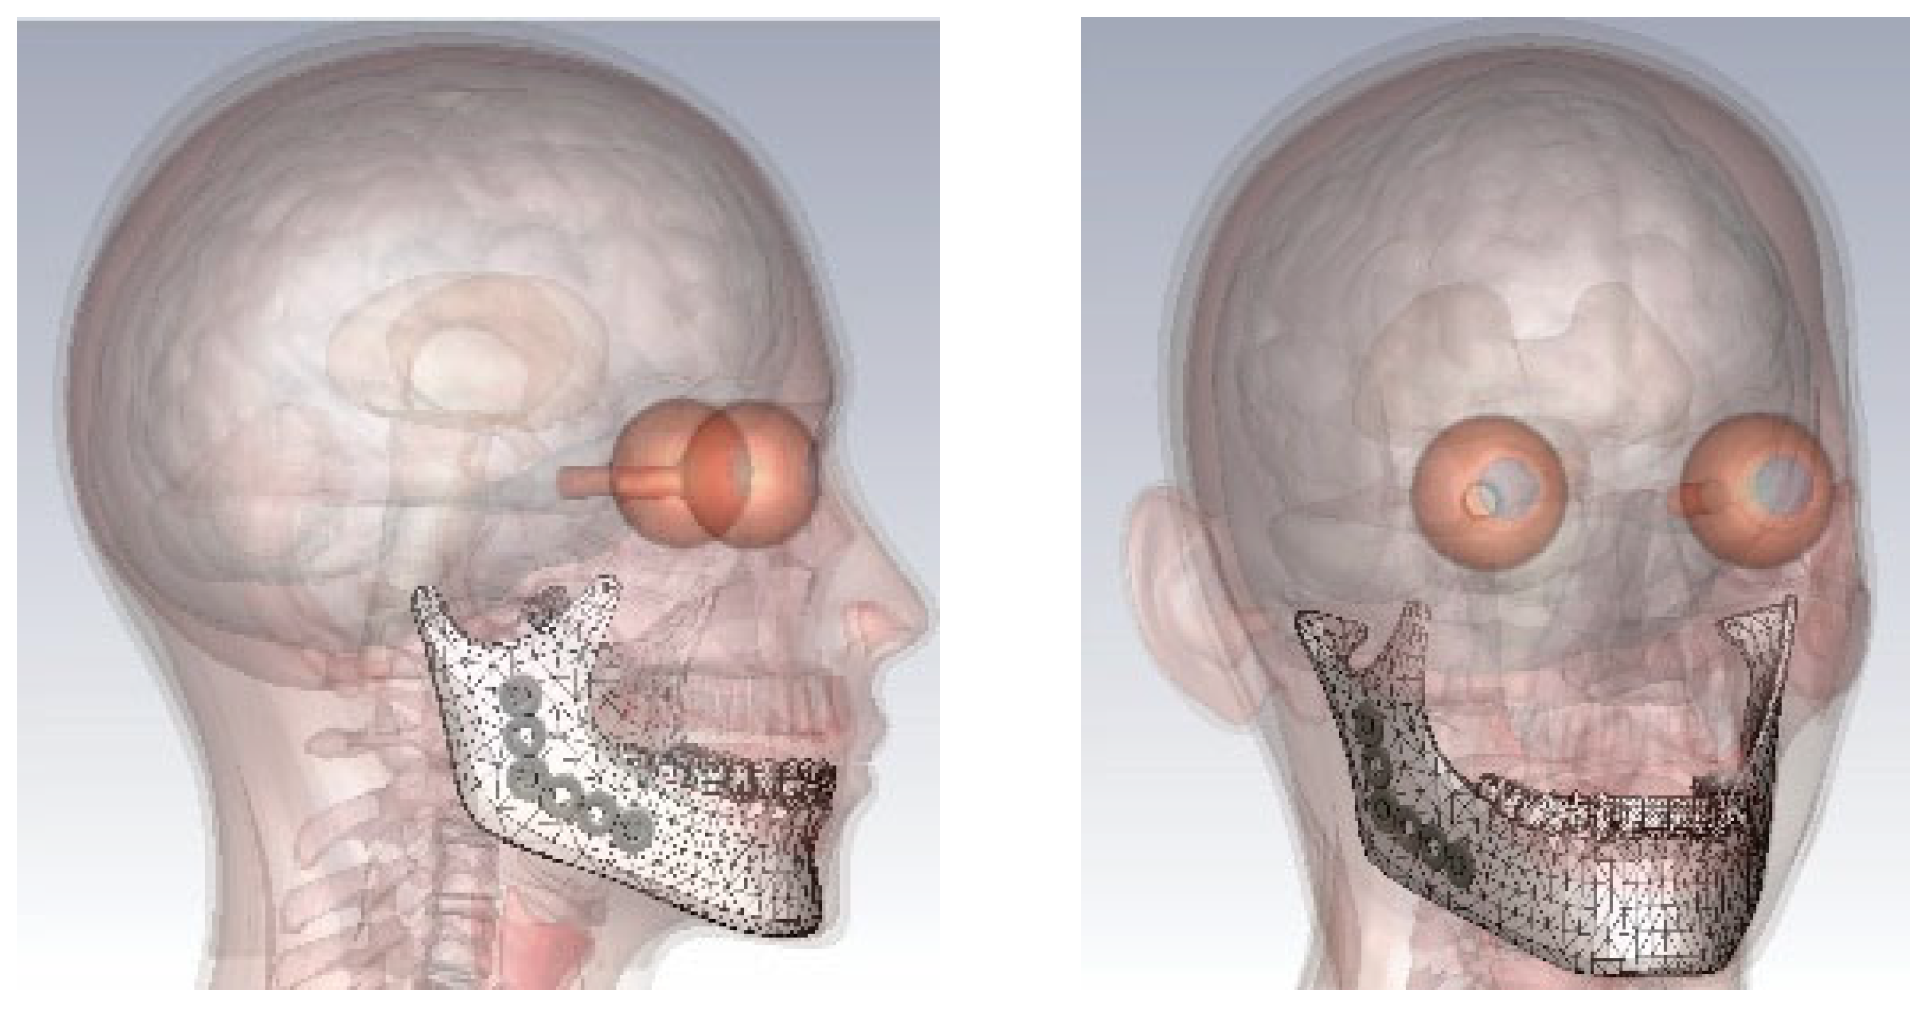

2.2. 3D Head Model

2.3. 3D Models of Titanium Plates and Screws

2.4. 3D Model of a Mobile Phone